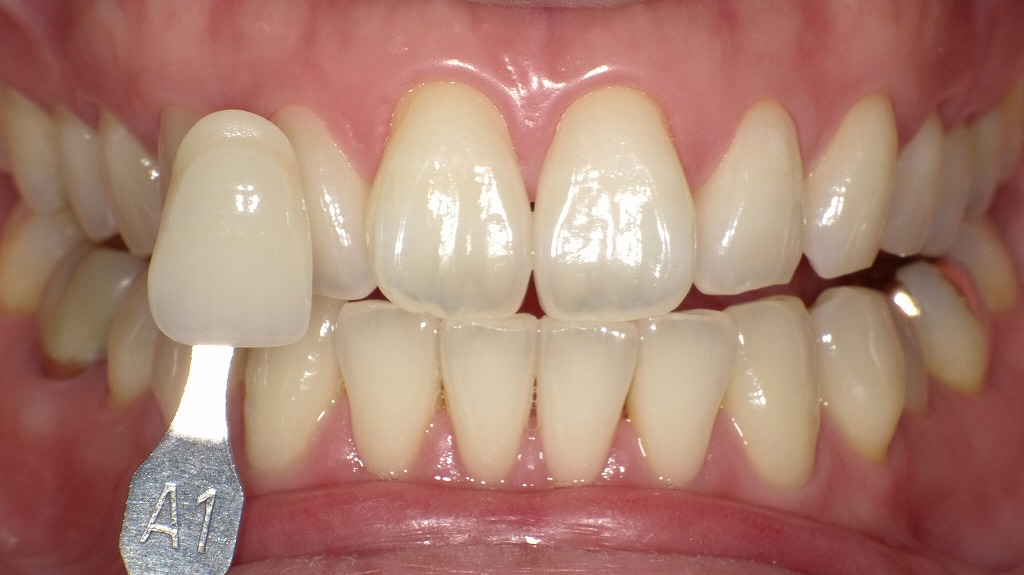

- 3.1.2.2. 2枚目:ホワイトニング後(A1シェードとの比較)

2枚目:ホワイトニング後(A1シェードとの比較)

2枚目では、シェードガイド「A1」が比較のために前歯の横に当てられており、

ホワイトニング後の歯がA1に非常に近い白さまでトーンアップしていることがわかります。

ポイント:

- 1枚目より明らかに白く、透明感も増している

- 自然な白さの中でも「明るさのレベル」が1段階以上アップ

- A1は「自然歯で達成できる最も明るい色のひとつ」